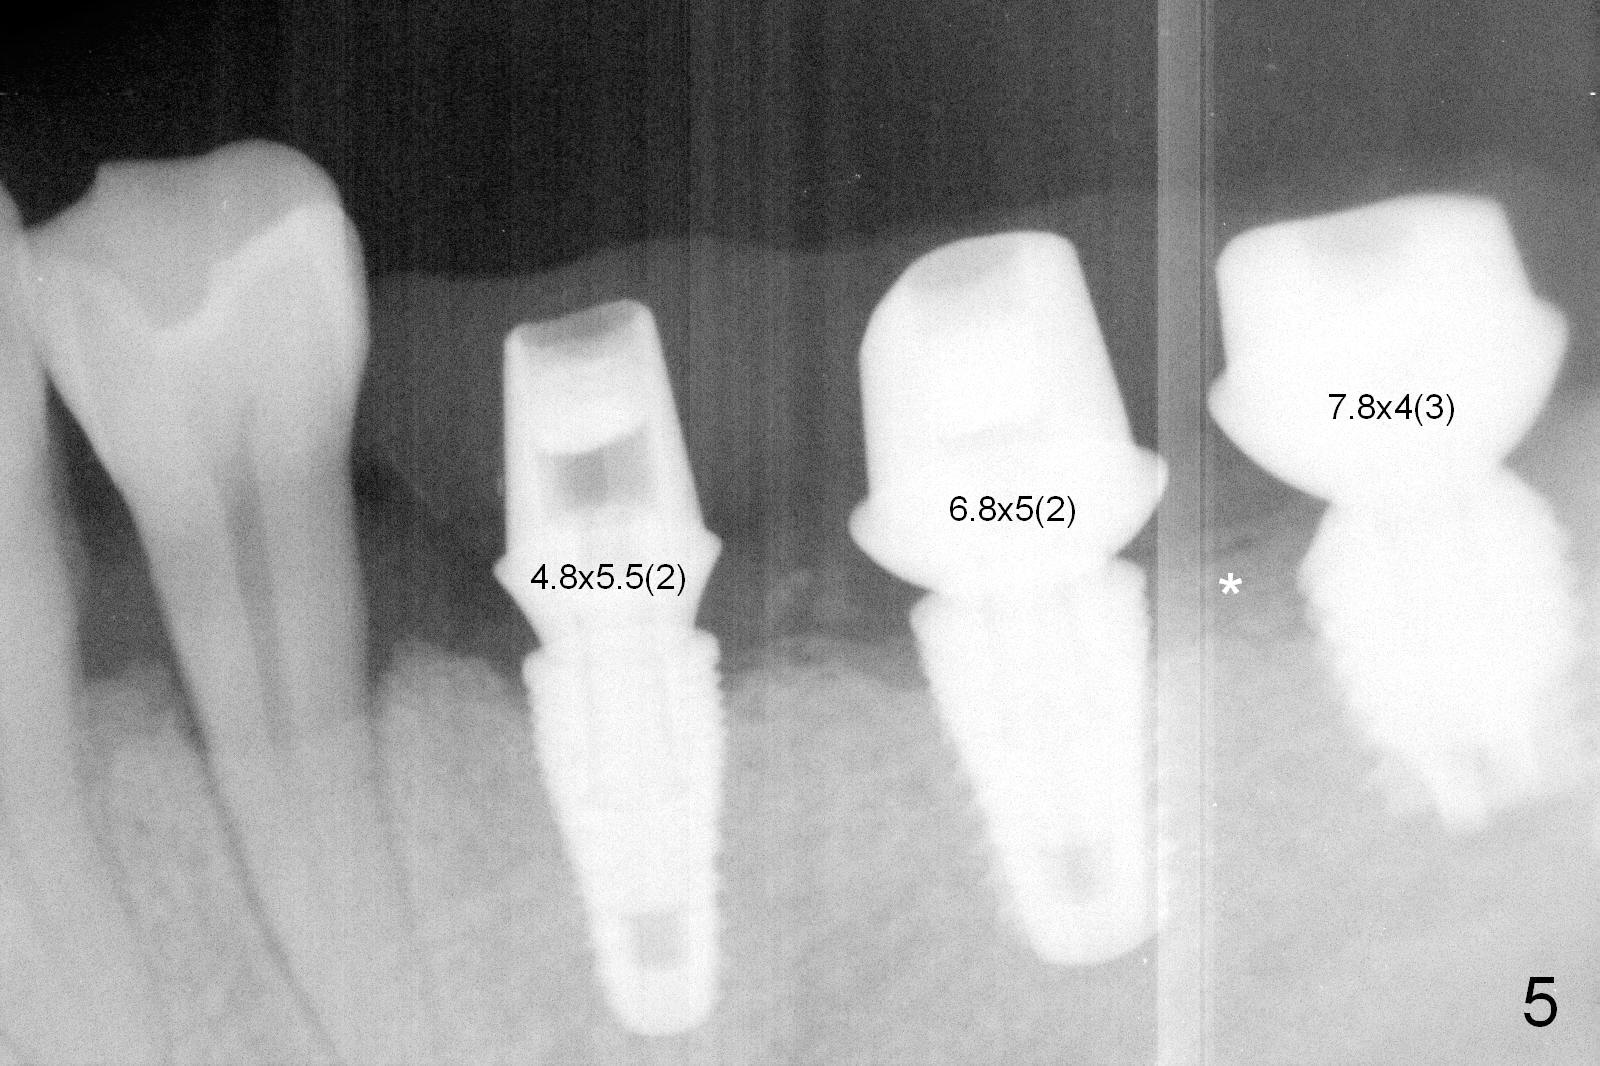

Although bone height is limited, the crest of the lower left area appears to be wide (Fig.1 arrowheads). Initial osteotomy depth is 6 mm (at #18) and 8 mm (19,20) with sufficient clearance from the Inferior Alveolar Canal (Fig.2 red dashed line). The size of the implants at the sites of #18-20 is shown in Fig.3 in millimeters. The insertion torque is around 50 Ncm. When abutments are immediately placed (the diameter and size shown in mm in Fig.4,5) and autogenous bone is packed around the implants/abutments, the ridge looks particularly wide (arrowheads). A splinted immediate provisional is fabricated.

The patient returns for final restoration 4 months postop. He is a smoker with poor oral hygiene. The provisional is fractured at #19 (distobuccal). There is a gap mesial to #18 abutment. It appears that there is mild bone loss, particularly mesial to the implant at #18 (Fig.5,6 *). The implants should have been placed deeper to prevent periimplantitis. When the abutment at #18 (7.8x4(3) mm) is removed, there is food debris mesial, although the gingiva remains healthy. A smaller abutment with shorter cuff is placed (6.8x4(2) mm) before impression.